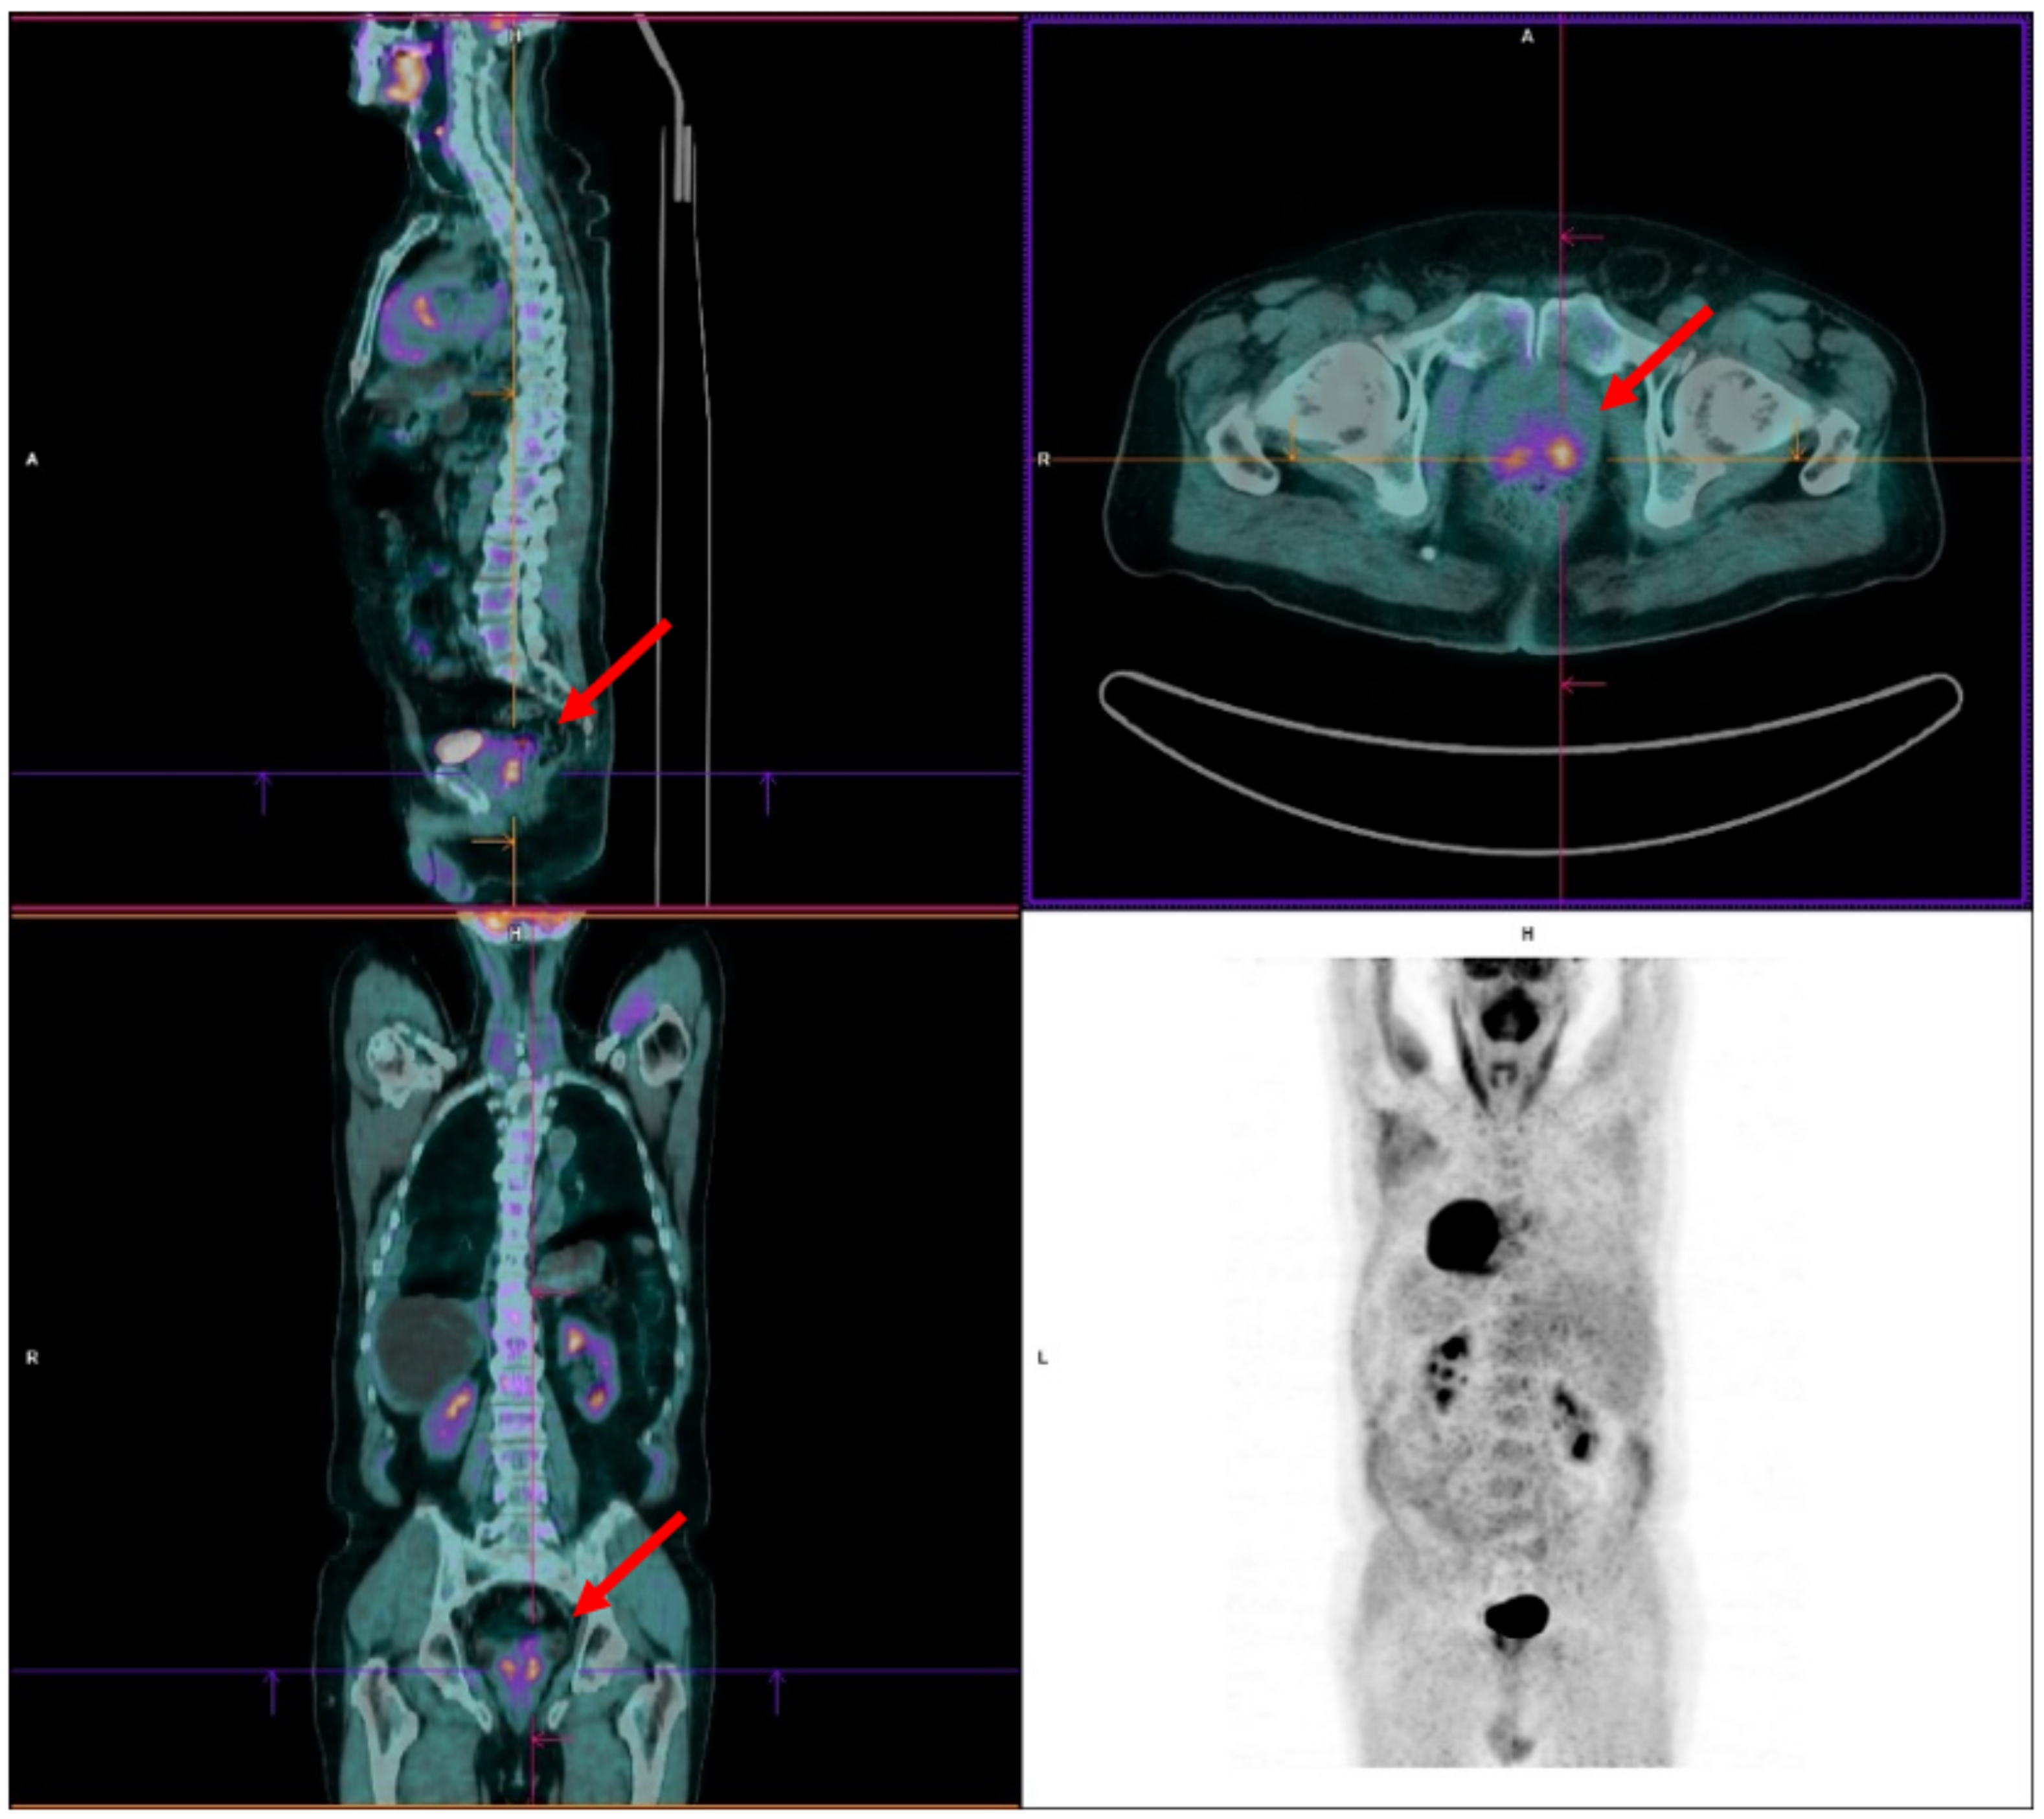

2. FDG PET in the Incidental Detection of the Primary PCa

4.1. Case 1

4.2. Case 2